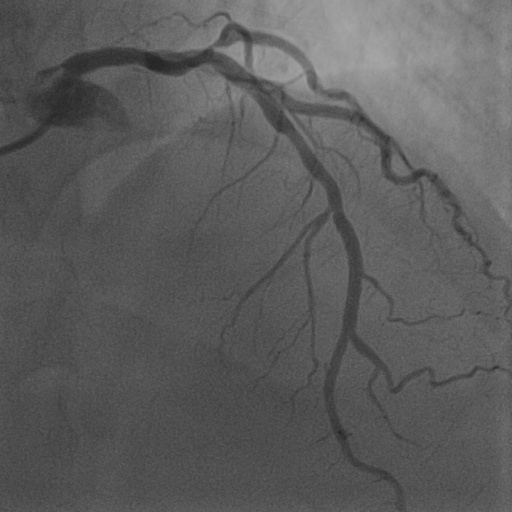

| Image | Ground truth | Video frame | Ground truth | Video frame | Ground truth |

| XCAD [33] | CADICA [19] | Our XACV dataset | |||

4.1 XACV Dataset

We collect 111 complete records of coronary artery X-ray videos, encompassing the injection, flow through the blood vessels around the heart, and dissipation of the contrast agent. Subsequently, we establish the XACV (X-ray Angiography Coronary Video) dataset. Each video consists of varying numbers of high-resolution coronary artery X-ray images. We invite experienced radiologists to annotate the vascular regions, focusing on one or two frames where the contrast agent is most prominent in each video. The XCAD dataset contains only a single image, and the CADICA video dataset does not provide corresponding ground truth. Therefore, in the following experiments, we conduct all the analyses on our collected XACV dataset and the corresponding GT for each sequence. In Figure 5, we show that compared to other publicly available datasets, XCAD [33] and CADICA [19], our dataset exhibits finer annotations in the vascular regions, providing an advantage for future related tasks. The development and use of our dataset have been approved by our institution’s IRB.